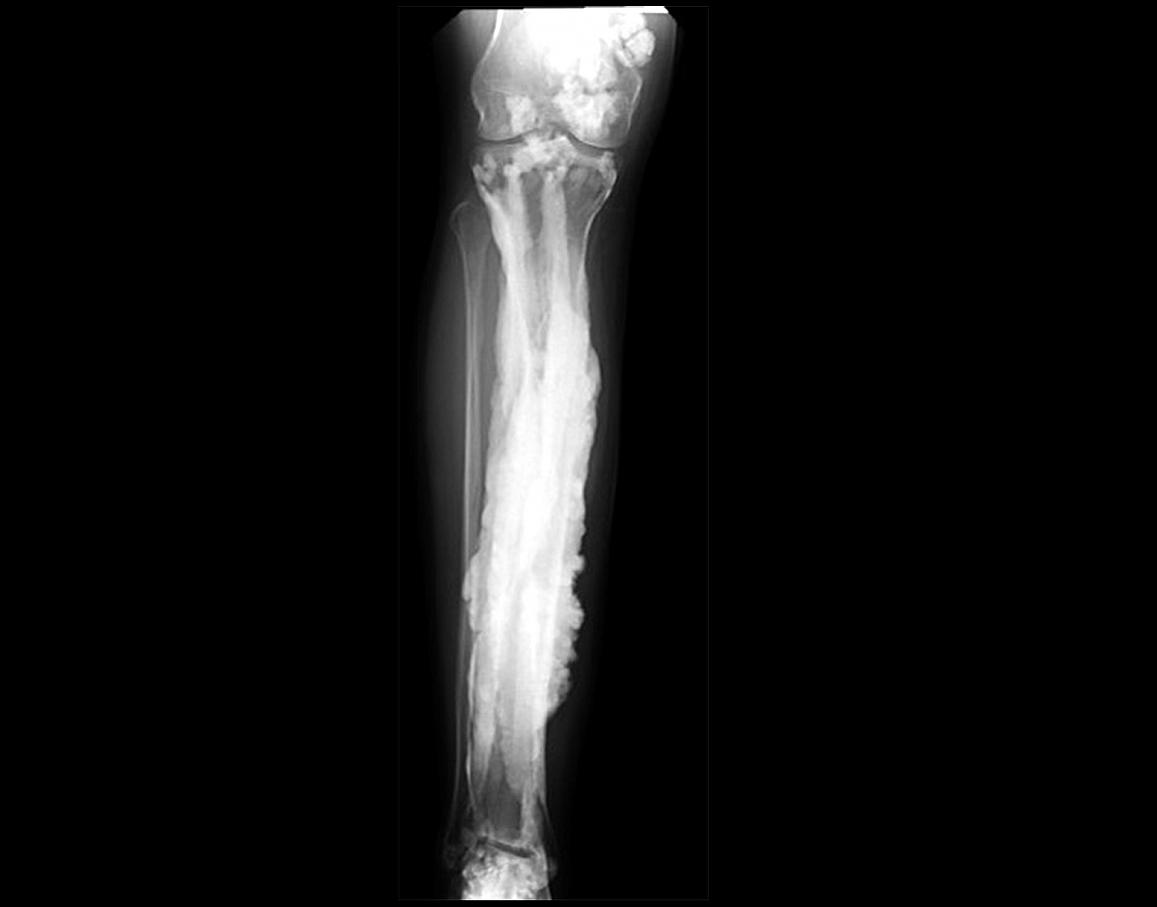

x-ray of bone with extra growths likened to dripping candle wax

An x-ray of a patient with melorheostosis NIH Image Gallery

Melorheostosis

“Dripping candle wax” is the classic descriptor applied to the x-rays of people with melorheostosis, a disorder where certain bones grow extra outer layers creating bulbous-like areas that resemble melting wax from a candle stick. The disease almost never affects both sides of the body equally, and is usually restricted to one part of the skeleton. It doesn’t even affect an individual bone evenly—the growths usually appear on only the right or the left side. Because of this unevenness, people with melorheostosis often end up with varying limb lengths, and the additional layers cause joint stiffness and pain.